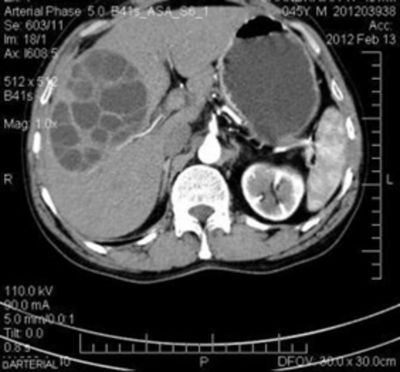

Hydatid cyst may arise anywhere in the body secondary to echinococcus infection. The daughter cysts of hydatid cyst may occur in two patterns: endogenous cysts and exogenous cysts. ENDOGENOUS CYST: Endogenous cysts are present within the main walls of the hydatid cyst as inward extension of lumen in the cystic mass EXOGENOUS CYST: The daughter cyst pushes the wall of main hydatid cyst and eventually disotrts the classic circular imaging pattern. Exogenous cysts are associated with recurrence after surgery. Reference: https://pubmed.ncbi.nlm.nih.gov/31749548/ Image via: https://ispub.com/IJPD/6/1/14471